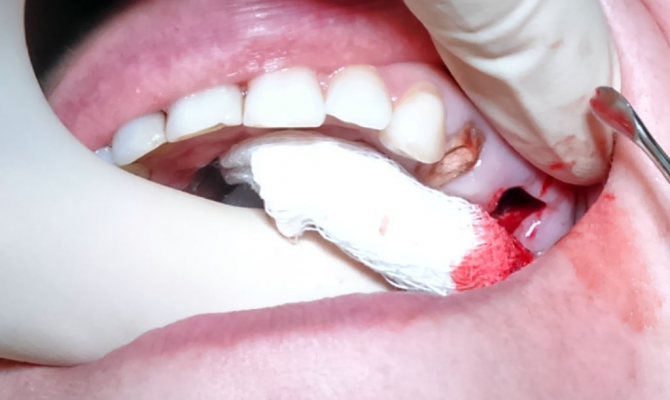

- Кровотечение из лунки зуба с включением пузырьков воздуха. При выдохе через нос численность пузырьков возрастёт.

Если в ранке нет осколков, пломбировочного материала и присутствия инфекции, то при таком раскладе стоматолог старается сформировать после удаления зуба сгусток крови в лунке и проследить за тем, чтобы образовавшаяся полость не была подвержена инфекции. Для подобных целей может применяться небольшой марлевый тампон, который пропитывается раствором йода. Сам по себе йод обладает хорошими бактерицидными свойствами, позволяющими быстро устранять все патогенные микроорганизмы.

Чаще всего такой тампон может самостоятельно фиксироваться в образовавшейся раневой полости после удаления зуба. Иногда требуется наложение швов на десну, которые делаются непосредственно стоматологом. Лечение при помощи йодового раствора делается на протяжении шести-семи дней вплоть до момента формирования грануляционной ткани, которая позволяет закрыть перфорацию.

- Провести мероприятия по предупреждению его инфицирования (наложение тампона с раствором йода).